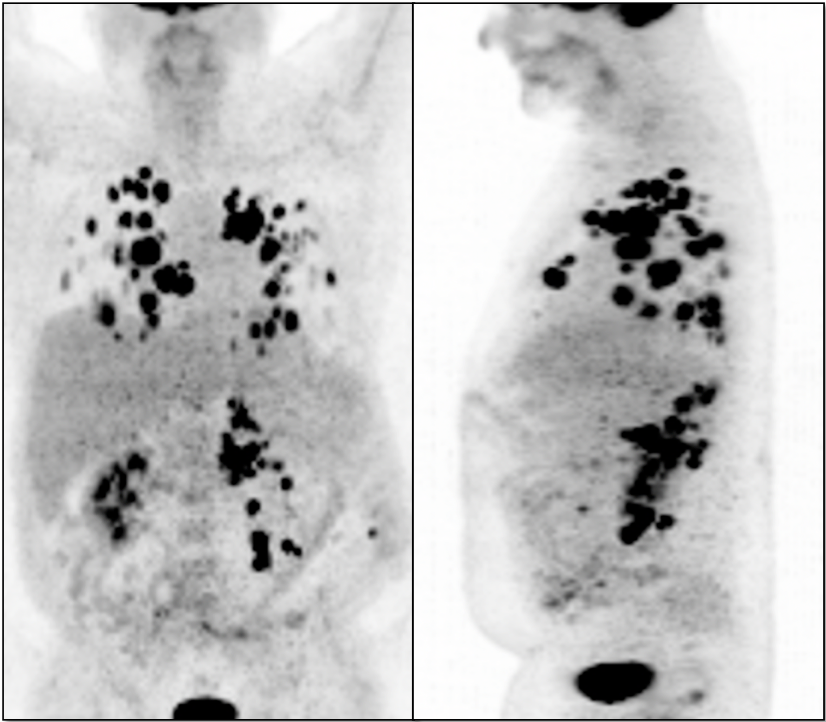

Metastatic Disease: Metastatic RCCA lesions are usually more FDG avid than the primary lesion (nearly all demonstrate metabolic activity greater than liver uptake).

• Hematogenous spread, often to lungs, bone, liver, and brain.

• Lymphatic spread to regional and distant lymph nodes.

• Can be useful diagnostic tool to assess potential regional or distant metastatic disease.

• PET/CT has high much higher sensitivity for metastatic lesions than for the primary lesion.

• PET/CT is utilized for patients with known or suspected recurrent disease (or at high risk for recurrence).